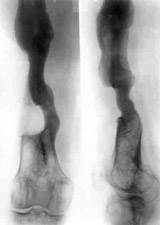

Results of treatment.Results of treatment.

Results of treatment.